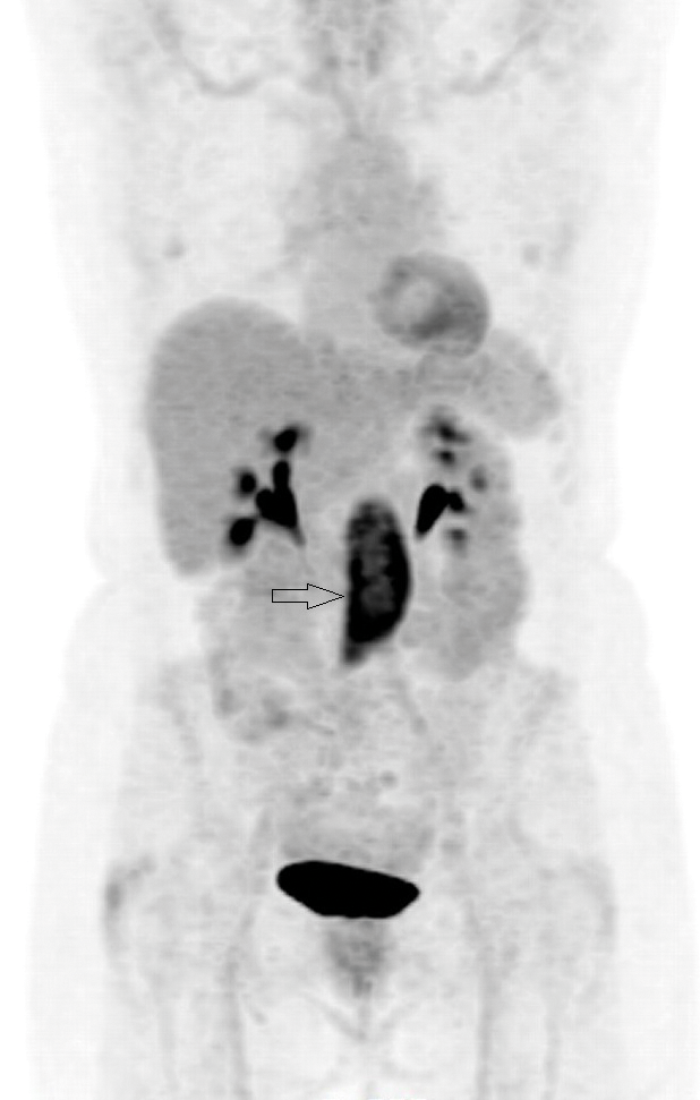

Figure 6: Coronal PET-CT image shows intense uptake

in the tissue seen on the axial image (arrow).

PET-CT with 18F-fluorodeoxyglucose (18F-FDG) can be used to ascertain if there is functional tissue with areas of increased glucose activity. Active RPF is seen as an area of increased uptake (Figures 5 and 6) and this can be used to assess if treatment has been successful. Uptake is seen in active inflammation but not if there is metabolically inactive disease [5]. However, lymphoma also demonstrates avid 18F-FDG uptake, so PET-CT cannot give a definitive diagnosis, but needs to be interpreted in conjunction with other imaging modalities.